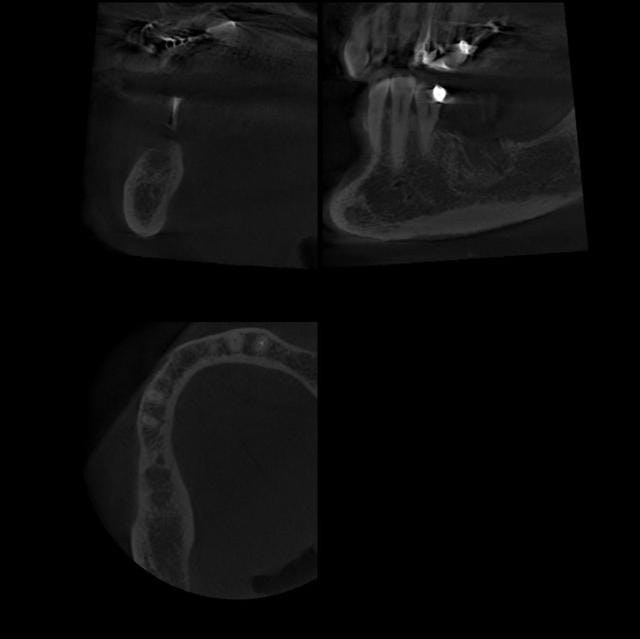

13/03/2007 à 08h25

Et voilà